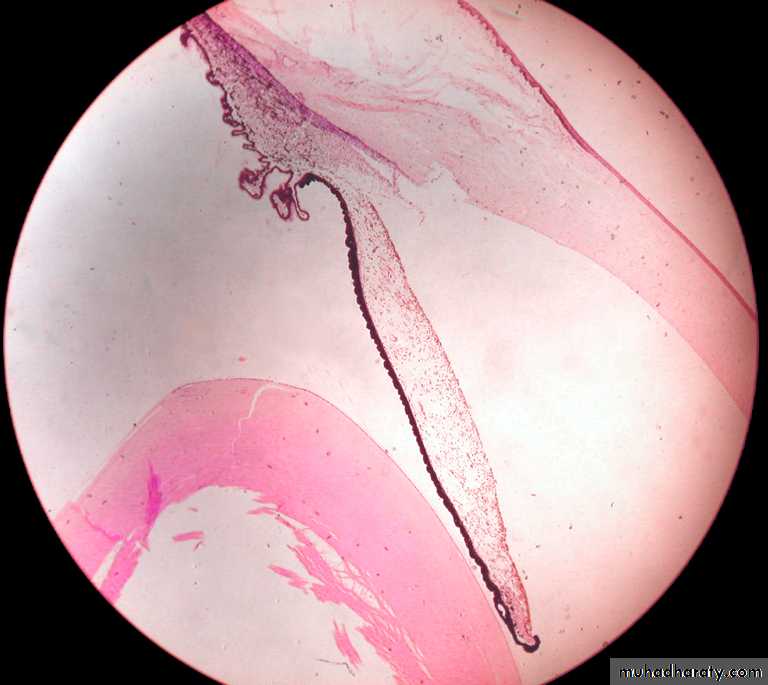

The Limbus

• In the corneoscleral junction the corneal cellular lamellae merge with the collagen fibers of the sclera

• Endothelial lined channels unite to form the canal of Schlemm draining the aqueous humour to the venous blood

A section through the corneoscleral junction (limbus) showing (A) The canal of Schlemm, (B) The Ciliary processes, and (C) The Iris.

C